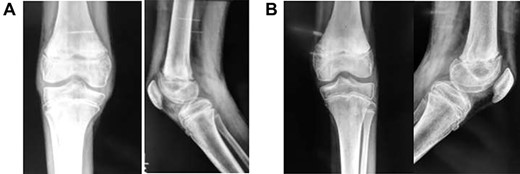

Follow-up was every 6 months over the next 5 years (Fig. 4A and B). Full range of motion was achieved in both limbs, with the child fully ambulatory and with no leg-length discrepancy. Future adult femur length does not appear to have been impacted.

(A) Frontal and lateral view of right knee at 6-months post-injury; (B) frontal and lateral view of left knee at 6-months post-injury

As it was a bilateral injury, gentle physiotherapy was started after plaster removal—only active and assisted-active movement was used, rather than force. Other studies have encouraged early physiotherapy post-plaster removal to reduce the risk of fixed-flexion deformity [3]—some suggest caution in using forcible manipulation for deformity correction [1]. The patient’s recovery has been excellent (Fig. 4A and B); long-term results demonstrate a full range of movement bilaterally with no distal neurological deficits. The patient can walk unassisted, has been observed running and is reportedly back to all routine activities.